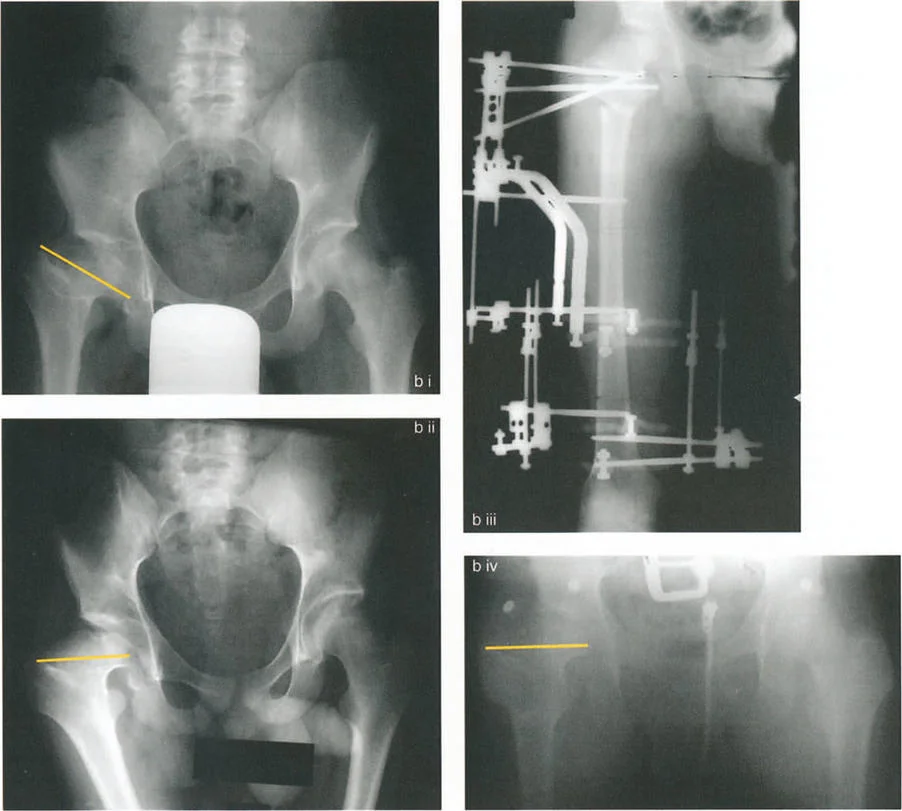

صور توضح حالة كسع الورك مع تضخم المدور الكبير بسبب مرض بيرثيز، وعلاجها باستخدام قطع عظم مورشر مع التثبيت الداخلي.

ب. قطع العظم الفاروسي (Varus Osteotomy)

- متى يستخدم: يُطبق في حالات فحج الورك (Coxa Valga)، حيث تكون الزاوية بين عنق وجسم الفخذ كبيرة جدًا، أو في حالات التهاب المفاصل التنكسي (الخشونة) لتحويل مناطق تحمل الوزن في المفصل، أو عندما يكون رأس الفخذ بيضاوي الشكل.

- الهدف: تقليل الزاوية بين عنق وجسم الفخذ، مما يزيد من ذراع الرافعة للعضلات المبعدة ويقلل الضغط على المفصل. قد يؤدي هذا إلى إزاحة المدور الكبير للأعلى، مما يستدعي إجراء نقل للمدور الكبير لتعويض هذا التأثير.

- التقنيات:

- قطع عظم نيشيو (Nishio Osteotomy): طورها نيشيو عام 1984. تتضمن قطعًا دائريًا (Dome Osteotomy) يقع وسطيًا للمدورين الكبير والصغير. يتم وضع مركز هذا القطع الدائري في مركز عنق الفخذ. يؤدي هذا إلى إزاحة المدور الكبير للأسفل والجانب، مما يعوض تأثير التقصير لقطع العظم الفاروسي ويحافظ على ذراع الرافعة للعضلات المبعدة أو يزيدها.

صورة توضيحية لقطع عظم نيشيو الدائري الذي يهدف إلى تقليل إزاحة المدور الكبير للأعلى.

تسلسل صور بالأشعة السينية يوثق تقنية نقل المدور الكبير بالمنظار، من إدخال سلك التوجيه والقطع إلى التثبيت بالمسامير.

صور بالأشعة السينية لحالة فتاة تعاني من تشوه فحجي مع دوران داخلي وخلع جزئي، توضح التدخل الجراحي بقطع عظم فاروسي مع نقل المدور الكبير والتثبيت بمثبت خارجي، ثم النتيجة النهائية بعد التعافي.